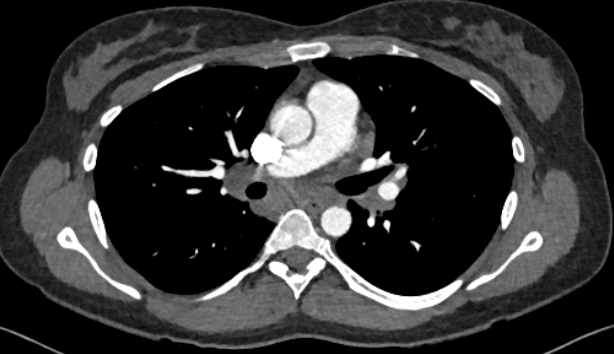

双侧对称性的非钙化性纵隔-肺门淋巴结肿大,未见明显占位效应。同时,影像检查中并未发现典型的病毒性肺炎特征,包括与COVID-19相关的异常表现。

CT肺动脉造影示双侧多发对称性非钙化的纵隔-肺门淋巴结肿大,对邻近结构没有占位效应。